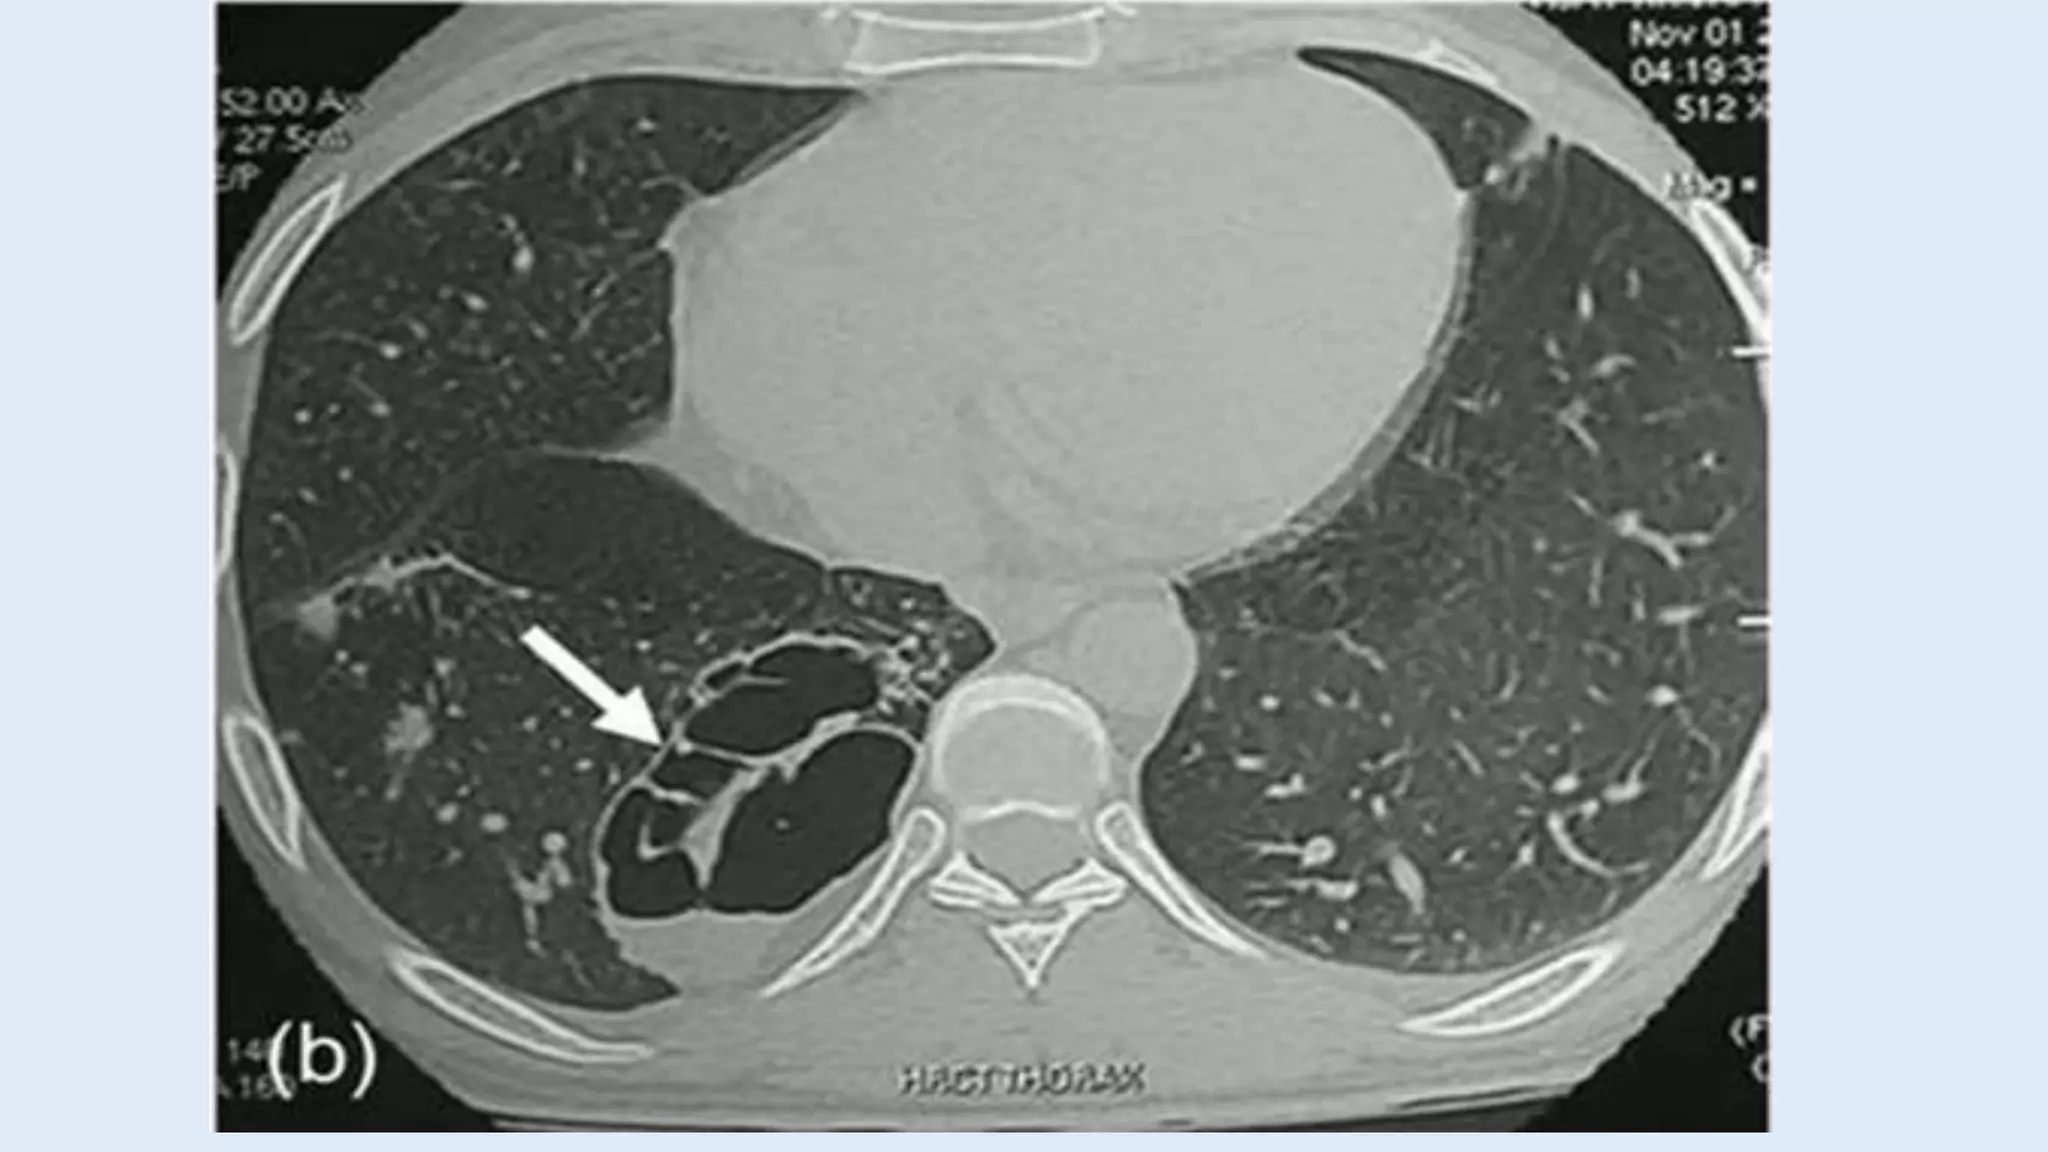

Computed tomography (CT)

• Most common appearance is a solid mass that may be

homogenous or heterogenous, sometimes with cystic

changes.

• Less frequently, a large cavitary lesion with an air-fluid level.

• Emphysematous changes at the margin of the lesion.

Computed tomography (CT) •Most common appearance is a solid mass that may be homogenous or heterogenous, sometimes with cystic changes. • Less frequently, a large cavitary lesion with an air-fluid level. • Emphysematous changes at the margin of the lesion.